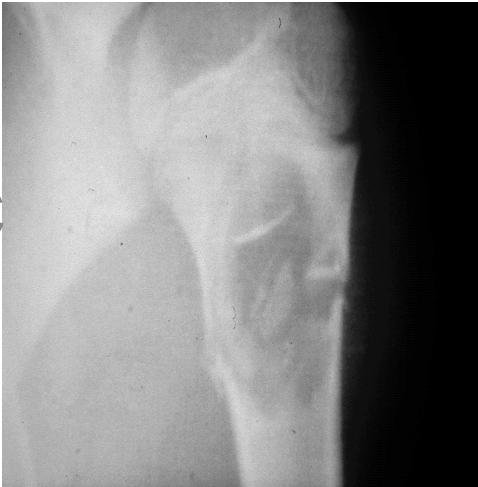

site: Distal shaft of femur size: matrix: Opaque, well defined, ossifying fibroma soft tissue involvement: no peristeal reaction